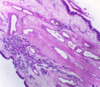

Diagnosis Describe Is this lesion neoplastic Arrow

Fibrocystic Disease of the Breast CYST FORMATION: Some ducts show cyst formation and become lined by cubical or flattened cells. APOCRINE METAPLASIA: Some ducts lined by acidophilic cells. FIBROSIS of the surrounding stroma. No Cystically dilated breast ducts